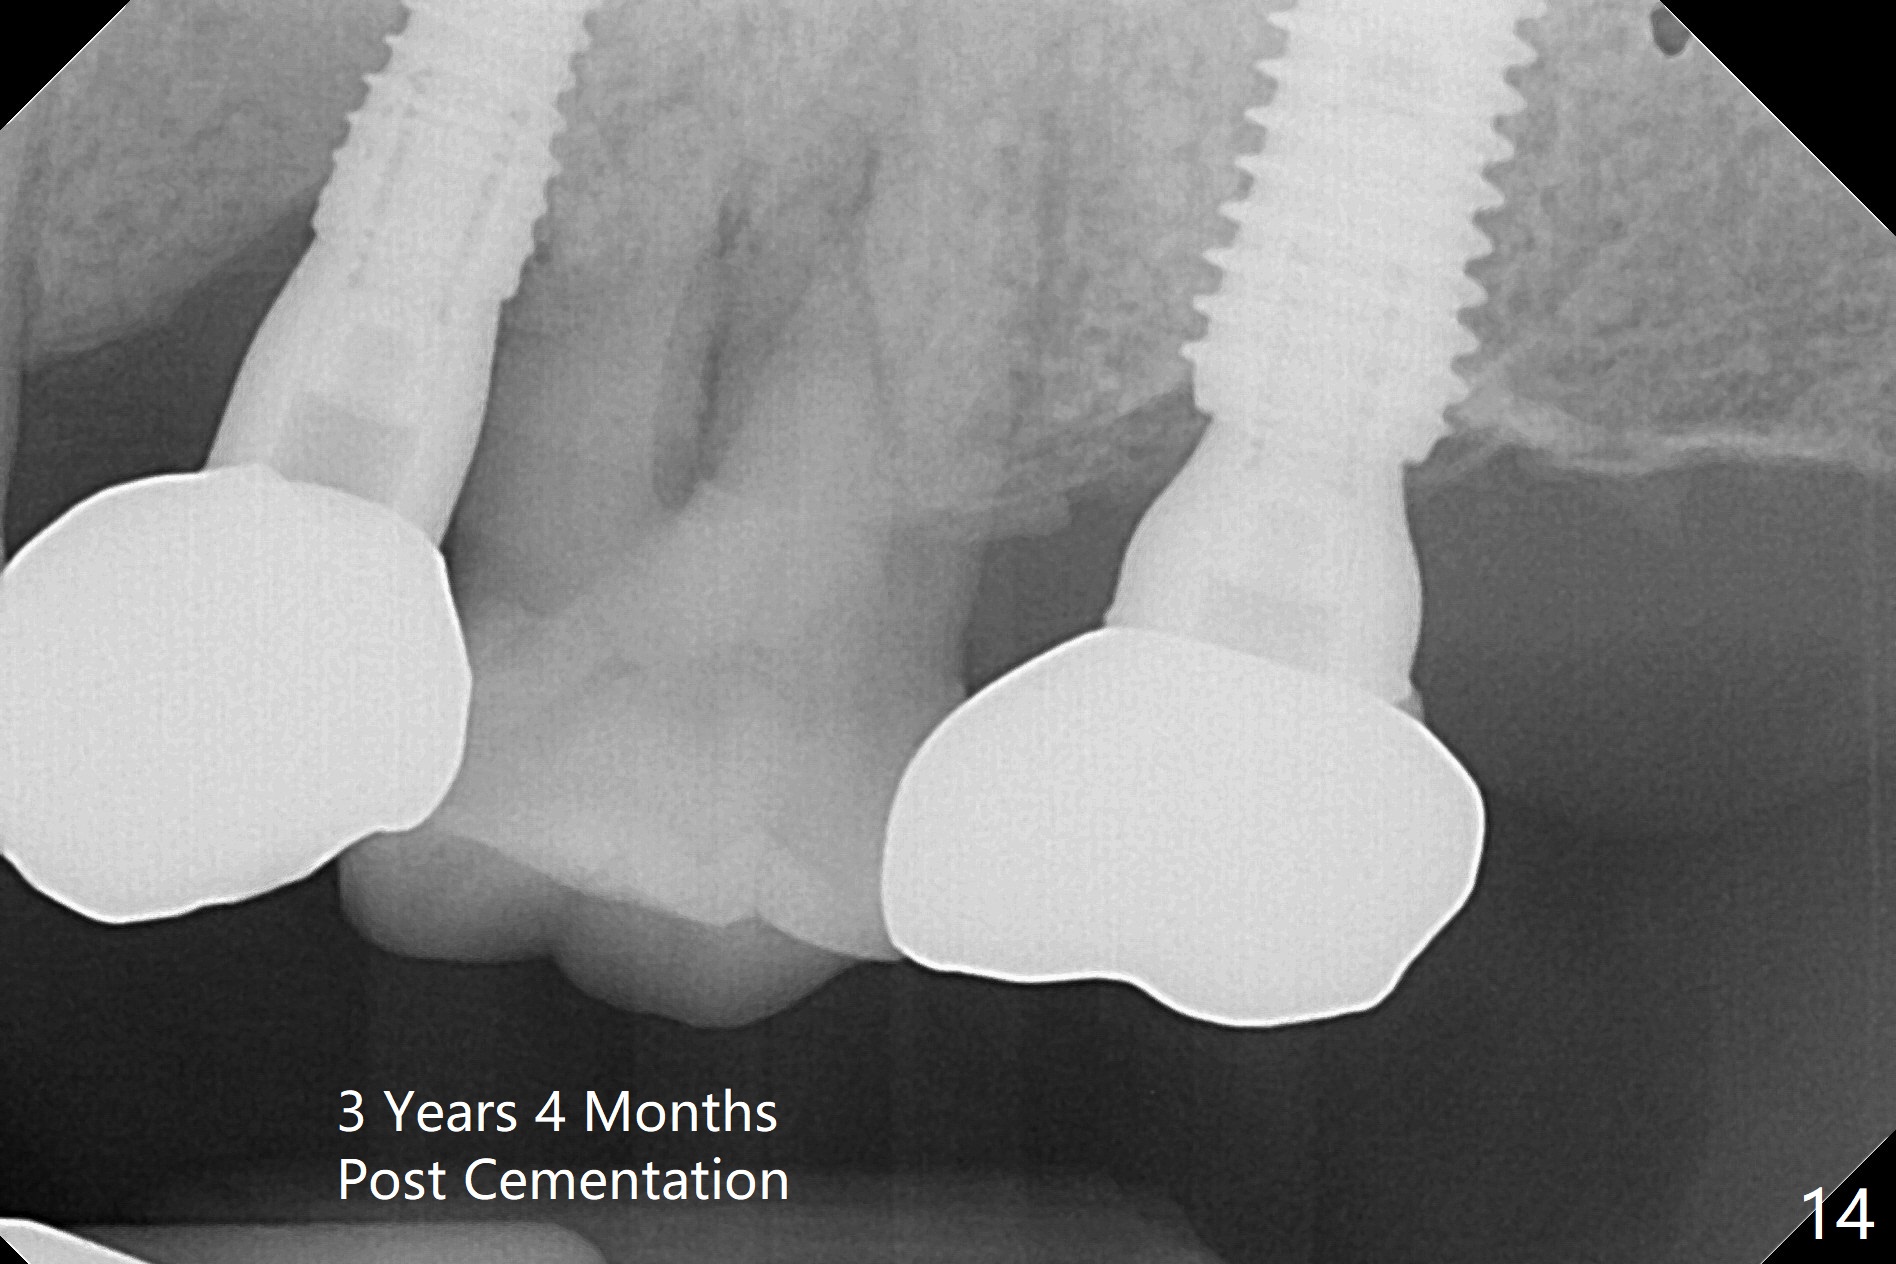

Initial osteotomy depth is 18 mm (Fig.1 green line) with 9 mm in the native bone (red line).  The bone density feels to be low.  There is at least 2 more mm bone apically (pink line).  The depth is increased by 2 mm so that when a 3.8x15 mm implant is placed, there is 10-11 mm implant/bone contact (Fig.2 red line).  There is large bony defect (Fig.3 *), which is bone grafted (Fig.4 *).  Finally a longer abutment is placed (4.5x5.5(5) in Fig.4 vs. 4.5x4(5) in Fig.2,3).  The 5 mm cuff does not look too long buccally (Fig.5) or palatally (Fig.6).   To prevent postop buccal gingival overgrowth (2), the buccal margin of an immediate provisional is subgingival (Fig.7-9 *).  Bone density between #13 and 14 appears to increase 3 months postop (Fig.10).  The implant seems to be equi-crestal (Fig.11 ^).  There seems to be more bone growth (i.e., decreasing gap) 6 months postop (Fig.12).  Impression is taken.  A crown is delivered nearly 7 months postop (08/07/2017).   While there is minimal bone loss at #13 and 15 three years and 4 months post cementation, the tooth #14 and 18 are mobile (Fig.13,14).